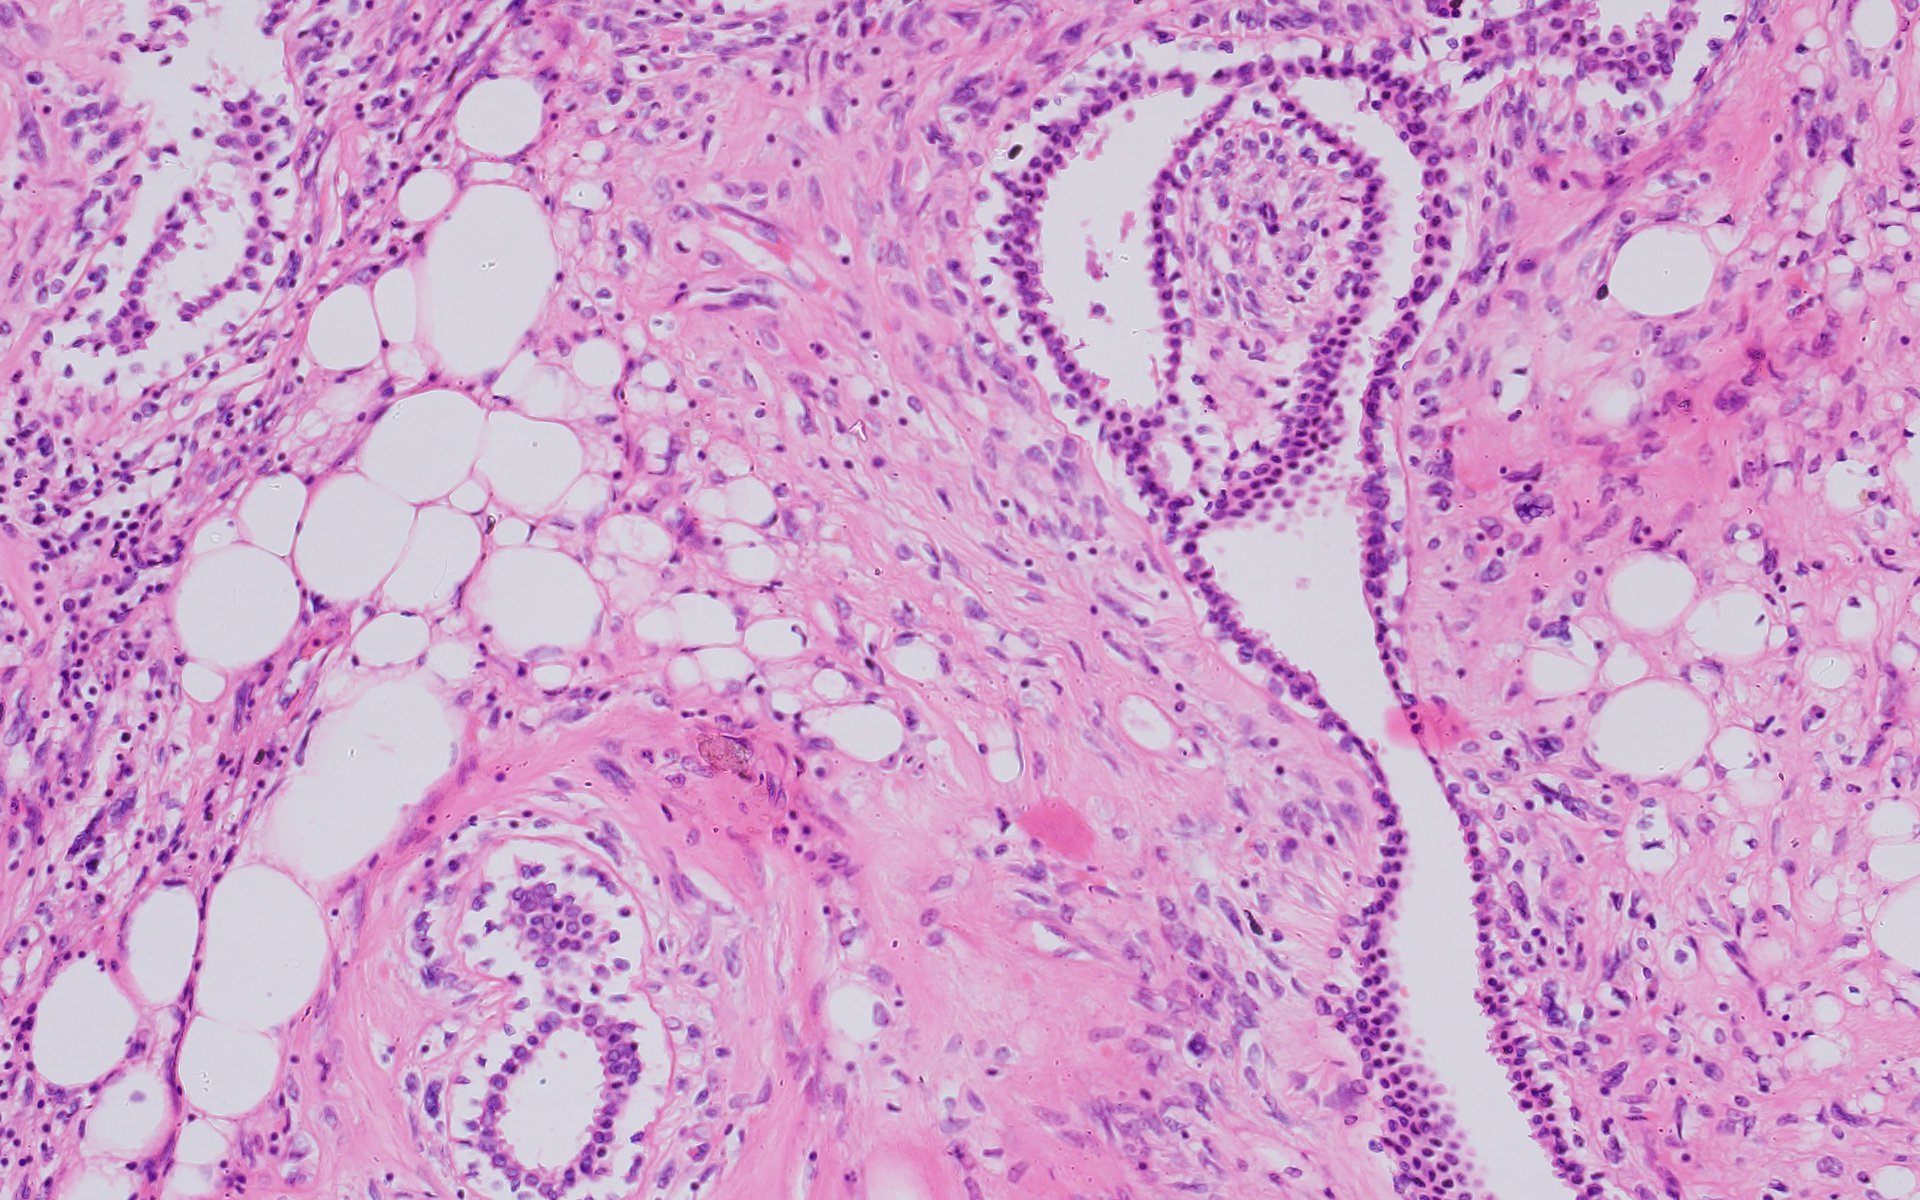

Physical examination revealed a 6.0?×?5.0 cm mass in the left breast. Mammography demonstrated an irregular, fat-containing, heterogeneous mass with circumscribed margins in the upper outer quadrant of left breast. Few scattered foci of coarse calcification were present within the mass. Breast sonography revealed an irregular, parallel, hyperechoic mass with circumscribed margins and no posterior acoustic features in the left breast at 3 o’clock position. Mild vascularity was observed on Color Doppler imaging. Contrast enhanced ultrasound (CEUS) done out of academic interest showed ill-defined, heterogenous enhancing mass, showing irregular shape, having surrounding vessels. Quantitative analysis showed higher PI (pulsatility index), AUC (area under curve) and lower TTP (time to peak) compared to normal tissue. The mass was assessed as Breast Imaging Reporting and Data System category 4b, and ultrasound-guided 14-gauge core biopsy revealed a biphasic tumor composed of bilayered ductal epithelium compressed by the proliferating stroma into leaf like architecture, The stromal cells showed increased cellularity, marked nuclear atypia and pleomorphism with round to oval nuclei, opened up chromatin, prominent nucleoli and moderate to abundant cytoplasm with many bizarre looking tumor giant cells. The stroma showed extensive heterologous lipomatous differentiation composed of neoplastic adipocytes as well as few lipoblasts. Mitosis was 3-4/10/hpf. Final histopathological diagnosis of malignant Phyllodes tumor with liposarcomatous differentiation was given. CT scan chest was done to look for lung metastasis, which revealed an irregular soft tissue mass in left breast with internal focal areas of fat attenuation. No nodules were seen in the lungs. Subsequent lumpectomy was performed and the gross specimen showed a well-demarcated tumor, measuring?6.8?×?6.5 × 3 cm. There were considerable bright yellow fatty components and some cleft-like spaces. Microscopically, the tumor exhibited a typical leaf-like growth pattern with extensive stromal overgrowth and stromal hypercellularity. Extensive areas of lipomatous differentiation were seen ranging from mature adipocytes to lipoblasts showing marked stromal atypia and irregularity. Mitotc activity was 7-8/10hpf. IHC for MDM2 was negative. Overall features were of malignant phyllodes tumor with well differentiated liposarcomatous differentiation.